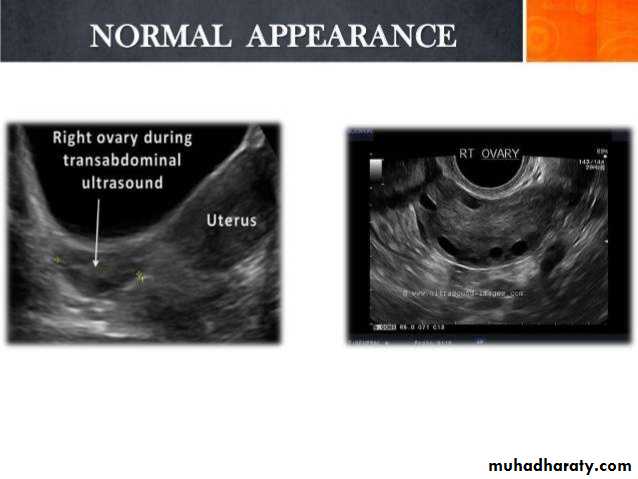

Ovarian cysts are commonly encountered in gynecological imaging, and vary widely in etiology, from physiologic, to complex benign, to neoplastic.Small cystic ovarian structures should be considered normal ovarian follicles unless the patient is pre-pubertal, post-menopausal, pregnant, or the mean diameter is >3.0 cm

Radiographic features

Ultrasound is usually the first imaging modality for assessment of ovarian lesions. Simple ovarian follicular cysts are:

anechoic

intraovarian or exophytic;

have an imperceptible wall

Ovaries